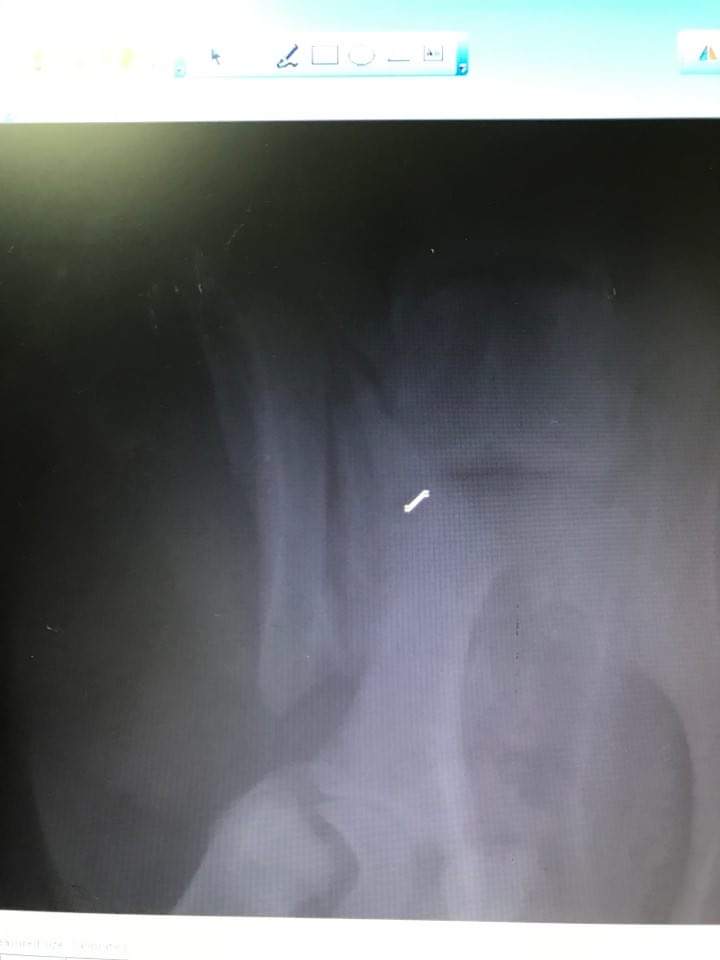

Verletzungen, Operationen

Leider sind diese Dinge immer wieder nötig! Erschreckende Bilder!